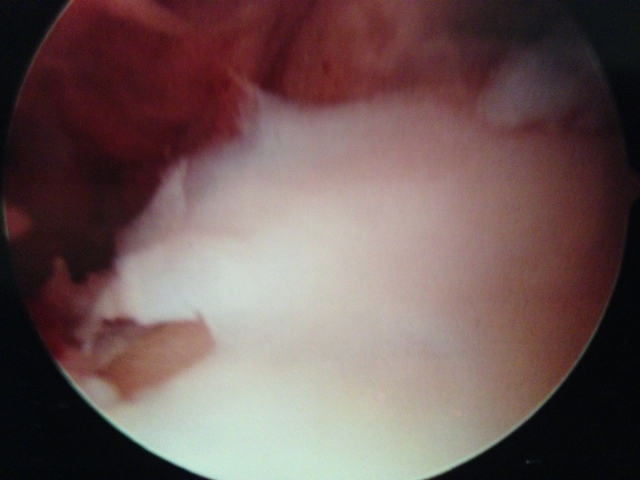

Action shot of microfracture of talus OCD.

Drill holes are then placed through the bone plate to allow bleeding in the area, which will aide in healing of the cartilage surface with fibrocartilage, which is a kind of scarring of cartilage.